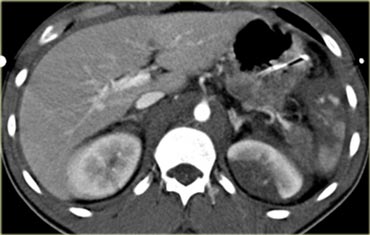

Trước tiên hãy quan sát các hình ảnh bên trái của bệnh nhân bị chấn thương gan.

Các dấu hiệu CT trong trường hợp này là gì?

Các dấu hiệu bao gồm:

- Mất tưới máu hoàn toàn thùy gan phải.

- Vùng ngấm thuốc cản quang (contrast blush) trong nhu mô gan, đồng thời lan ra ngoài bờ bên của gan.

- Tràn máu ổ bụng (Hemoperitoneum).

- Một vùng ngấm thuốc cản quang thứ hai ở mức thấp hơn.